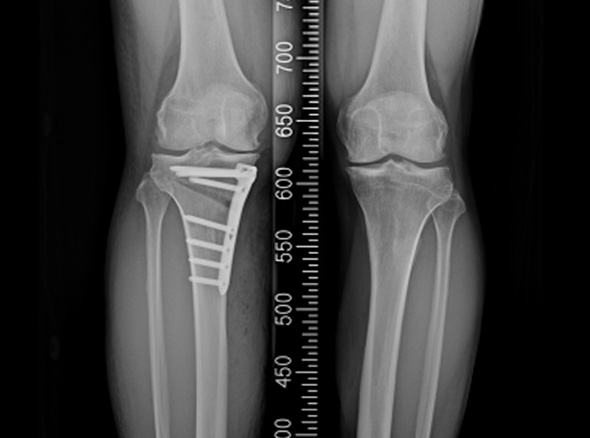

한국인의 대부분에게서 무릎 내측에 무릎 관절염이 발생됩니다.

관절염의 수술적 치료로는 인공관절 수술이 가장 흔하지만, 인공관절 수술을 할 만큼

연골 손상이 심하지 않다면 내측으로 치우친 체중 부하를 정상적인 외측 관절로

이동시키는 ‘무릎관절 교정 절골술’을 시행합니다.

* 환자에게 받은 소중한 자료입니다.

※ 금속판과 나사는 수술 후 약 1~2년 후 제거합니다.